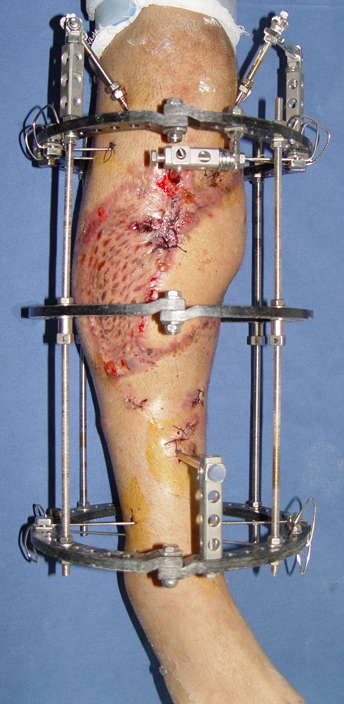

Pseudarthrosis of fracture and pseudarthrosis treatment is currently important problem for orthopedic surgery. Various treatment modalities have been described for pseudarthrosis treatment. All of the treatment methods include high complication rates and additional problems. Leg-length discrepancy, deformity and soft-tissue loss and chronic infection can concomitance with pseudarthrosis. Many internal or external fixation techniques have been described for pseudarthrosis.

Debridement and resection of bone fragment from the pseudarhtosis area vascularized or nonvascularized fibula graft, vascularized muscle flaps, bone grafting followed internal fixation techniques make a option for treatment of pseudarthrosis treatment. But these treatment modalities may not correct deformity and leg-length discrepancy.

Recently, ilizarov techniques which is basis depend on distraction osteogenesis , bone segment transport or acute shortening after the resection at the site of pseudarthrosis combined with lengthening at another level of bone have been used. These treatment techniques may include some advantage for problems of infection, leg-length discrepancy, soft-tissue loss, and joint contracture.